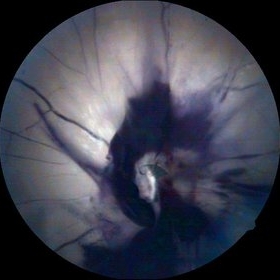

Rerinal Detachment with PVR

Sep 10 2014 by Mehul A Shah

A myopic male patient 35-years-old presented to outdoor and found to have retinal detachment with multiple fixed folds.

Photographer: Drashti Netralaya,Dahod

Imaging device: FF 450

Condition/keywords: proliferative vitreoretinopathy (PVR)